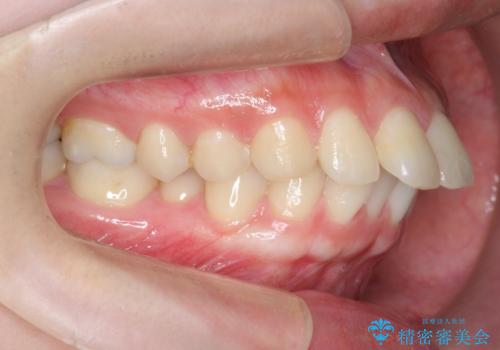

カリエール・マイクロインプラントを用い、時間はかかりましたが大きく歯の後方移動が達成され、前歯の見た目が大きく改善されました。

大きな後方移動を達成するにはマイクロインプラントと日常的なゴムかけが大切です。